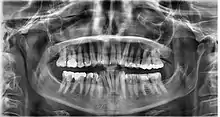

Dental